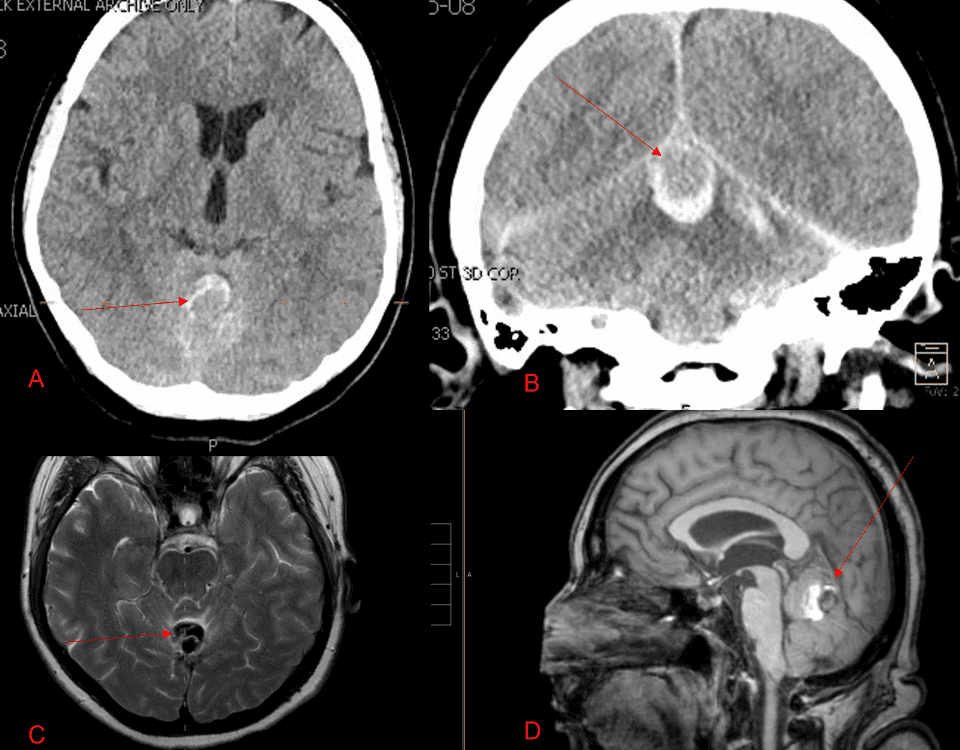

A 55-year-old woman presented with acute onset of severe headache, and possible witnessed seizure. Imaging confirmed intraventricular hemorrhage primarily focused within the fourth ventricle with diffuse […]